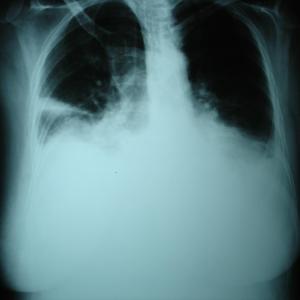

Breath-holding may predict adverse outcomes in COVID-19 patients